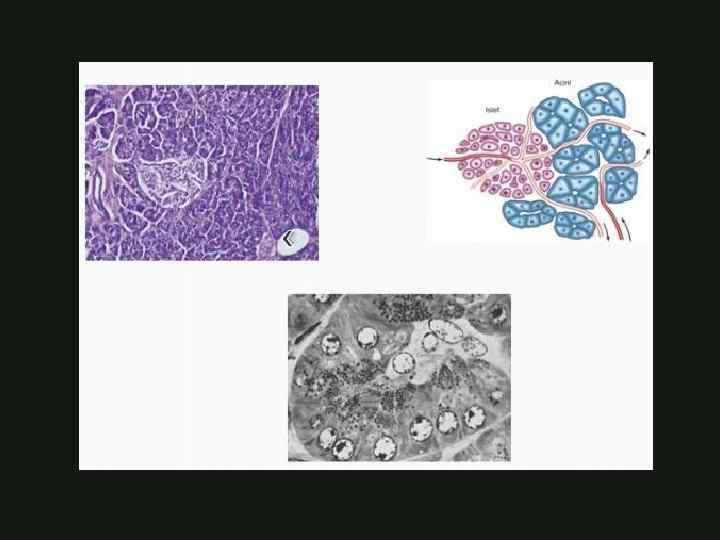

ГИСТОЛОГИЯ И ФИЗИОЛОГИЯ Эндокринная функция – островки Лангерганса (глюкагон, инсулин, соматостатин, вазоактивный пептид, панкреатический полипептид) КАФЕДРА ХИРУРГИИ МОСКОВСКОГО ФАКУЛЬТЕТА

ГИСТОЛОГИЯ И ФИЗИОЛОГИЯ Эндокринная функция – островки Лангерганса (глюкагон, инсулин, соматостатин, вазоактивный пептид, панкреатический полипептид) КАФЕДРА ХИРУРГИИ МОСКОВСКОГО ФАКУЛЬТЕТА

ГИСТОЛОГИЯ И ФИЗИОЛОГИЯ Экзокринная часть – ацинусы и выводные протоки (90% общей массы поджелудочной железы) - Протеолитические (трипсин, химотрипсин) - Липолитические (липаза, фосфолипаза) - Гликолитические (амилаза) КАФЕДРА ХИРУРГИИ МОСКОВСКОГО ФАКУЛЬТЕТА

ГИСТОЛОГИЯ И ФИЗИОЛОГИЯ Экзокринная часть – ацинусы и выводные протоки (90% общей массы поджелудочной железы) - Протеолитические (трипсин, химотрипсин) - Липолитические (липаза, фосфолипаза) - Гликолитические (амилаза) КАФЕДРА ХИРУРГИИ МОСКОВСКОГО ФАКУЛЬТЕТА